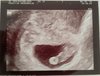

I tu moj chyba Mikolaj ssajacy paluszka [emoji173]️ Zobacz załącznik 905519